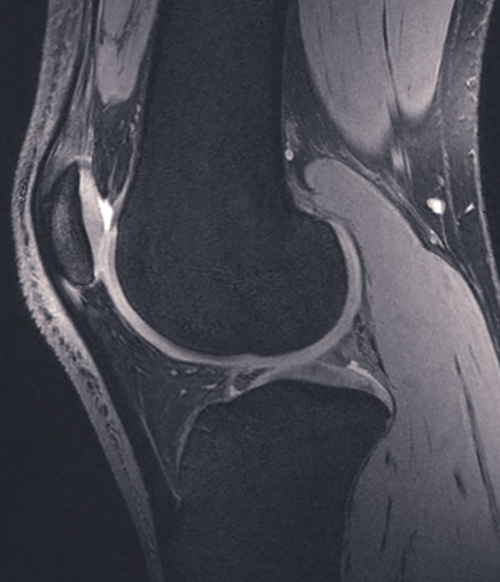

Một trong những chuyển giao công nghệ thiết yếu nhất giữa hai lĩnh vực này là kỹ thuật giao thoa thường được các nhà thiên văn sử dụng để thu hình ảnh có độ phân giải cao của bầu trời ở bước sóng vô tuyến. Kỹ thuật giao thoa chính là kỹ thuật mô phỏng hiệu ứng của một đĩa rất lớn bằng cách tổng hợp điện tử các tín hiệu từ nhiều kính thiên văn vô tuyến đơn đĩa nhỏ, và các kính nhỏ này được bố trí ở nhiều nơi có khoảng cách rất xa nhau. Kỹ thuật tổng hợp dữ liệu từ nhiều kính thiên văn để tạo ra một hình ảnh duy nhất được gọi là “tổng hợp khẩu độ”, được Martin Ryle, một nhà thiên văn vô tuyến từng đạt giải Nobel Vật lý phát triển. Một ứng dụng quan trọng của kỹ thuật này là phương pháp Cộng hưởng từ (MR) nhằm nâng cao độ chi tiết của hình ảnh và giảm thời gian soi quét trong các chẩn đoán y khoa. Chụp cộng hưởng từ (MRI) sử dụng các nam châm mạnh và các xung tần số vô tuyến để phân cực và kích thích các proton đơn lẻ trong phân tử nước trong mô người. Khi các xung bị tắt, các proton bị kích thích sẽ “thả lỏng ra” và phát ra sóng vô tuyến. Những sóng này được quan sát và ghi lại bởi thiết bị thu tần số vô tuyến trong máy MRI, sau đó sẽ được xử lý thành hình ảnh tương tự như hình ảnh giao thoa.

Kỹ thuật thiên văn dùng để tổng hợp dữ liệu từ nhiều kính thiên văn nhằm tạo ra một hình ảnh duy nhất, được gọi là “tổng hợp khẩu độ”. Kỹ thuật này đã được áp dụng cho cộng hưởng từ (MR) để tăng các chi tiết hình ảnh và làm giảm thời gian soi, quét trong chuẩn đoán y tế.